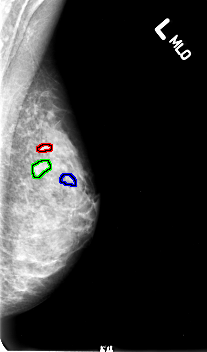

B_3005_1.LEFT_MLO

LEFT_MLO LINES 4568 PIXELS_PER_LINE 2688 BITS_PER_PIXEL 12 RESOLUTION 50 OVERLAY

FILE: B_3005_1.LEFT_MLO.OVERLAY

TOTAL_ABNORMALITIES 3

ABNORMALITY 1

LESION_TYPE CALCIFICATION TYPE PUNCTATE-AMORPHOUS-PLEOMORPHIC DISTRIBUTION CLUSTERED

ASSESSMENT 4

SUBTLETY 3

PATHOLOGY MALIGNANT

TOTAL_OUTLINES 1

BOUNDARY

ABNORMALITY 2

ABNORMALITY 3